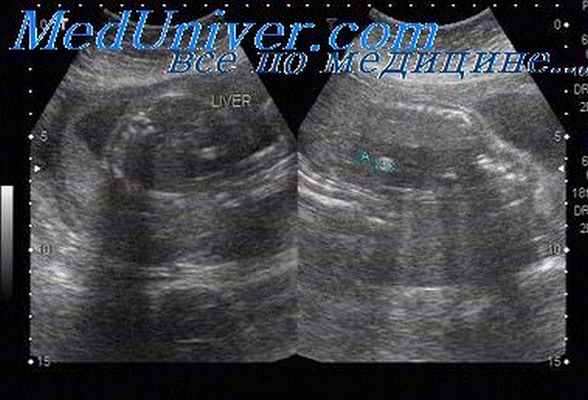

Синдром Холта-Орама (Holt-Oram) включает пороки сердца и аномалии развития верхних конечностей (фокомелия в 4,5%, аплазия лучевой кости, трехфаланговый большой палец кисти, клинодактилия).

Диагностика. Пороки сердца включают дефекты межпредсердной (30-60%) и межжелудочковой перегородки, открытый артериальный проток, дефект закладки эндокардиальных подушек, гипоплазию левого желудочка и нарушения проводимости, при этом в 17% случаев наблюдаются сочетанные пороки сердца. Состояние кистей при аплазии лучевых костей варьирует от труднодиагностируемого трехфалангового большого пальца до очевидной косорукости. Также может выявляться аплазия большого пальца кисти.